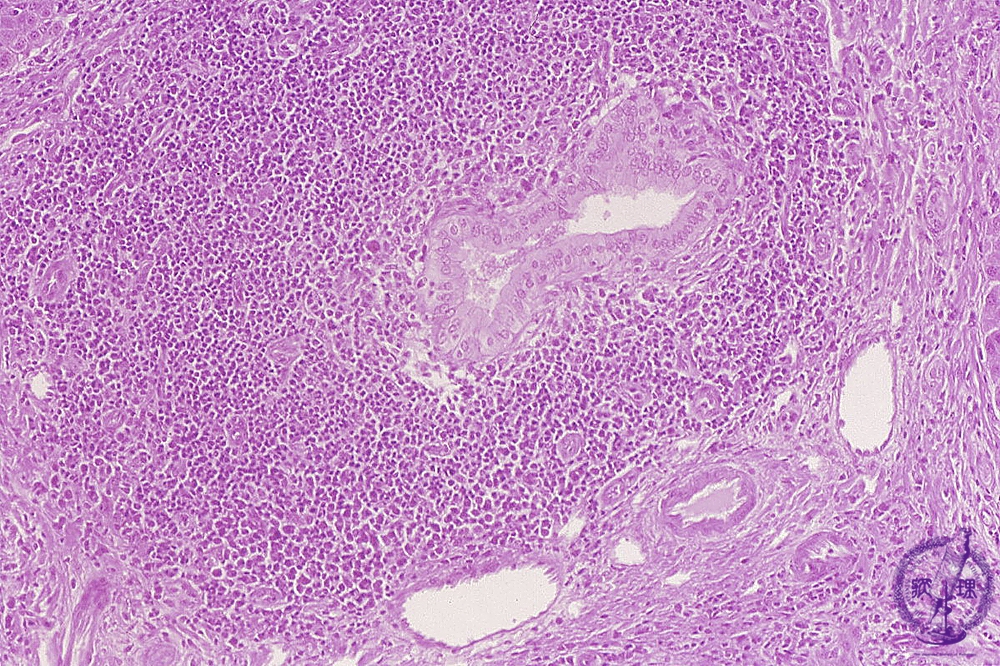

- 10.Liver

- (4)Primary biliary cirrhosis

Microscopic image (HE stain, intermediate power): There is a marked lymphocytic infiltrate (yellow circle) around bile ductules (image, center ・ black dot) within expanded portal areas and the bile ductular epithelium is damaged. These changes are characteristic of chronic non-suppurative cholangitis.

Click the image to see the enlarged image.